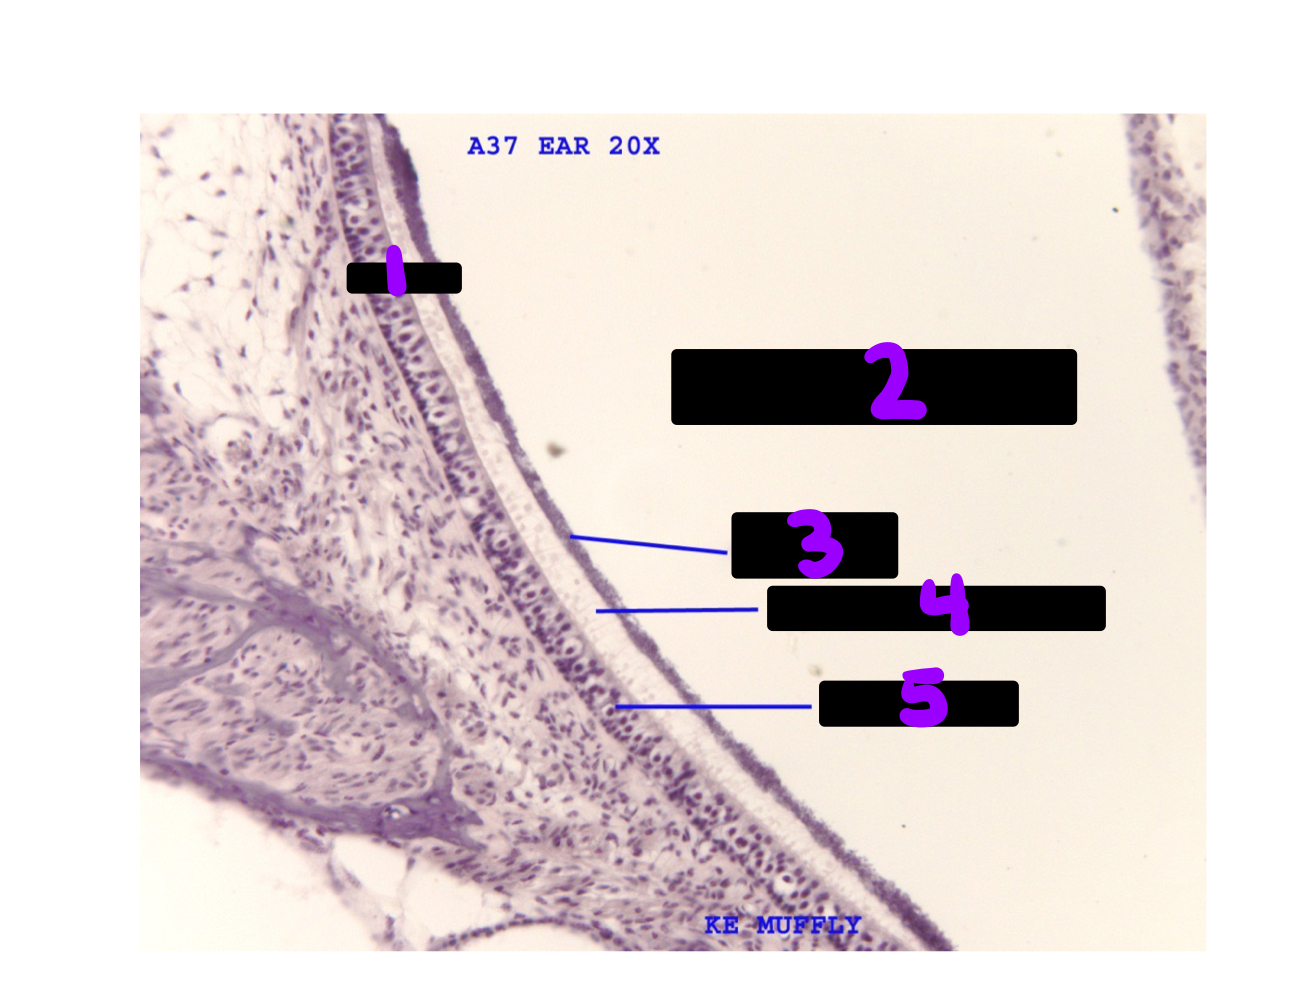

Q

What is #6-10?

A

1. Outer tunnel

2. stria vascularis

3. spiral ligament

4. inner spiral tunnel

5. inner hair cell